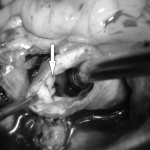

In the cardiac surgery departments of the V.P. Polyakov widely use various techniques for mitral valve reconstruction.

Mitral valve reconstruction is considered worldwide to be the optimal surgical treatment for mitral valve dysfunction for any etiology of the disease.

In addition, biological prosthetic heart valves made from animal tissues are subject to degradation after 10–15 years (or even earlier!) (they fail due to changes in the structure of the valve leaflets). In such a situation, a repeat operation to replace the heart valve is necessary. Risk of surgery! The average mortality rate during mitral valve reconstruction surgery ranges from 1 to 2%, compared with 5 to 7% for replacement (Society for American Thoracic Surgeons 2021 Harvest 1 Executive Summary). As the head of the cardiac surgery department No. 11 of the Regional Clinical Children's Hospital named after V.P. explains. Polyakova Dmitry Valerievich Kuznetsov , timely surgical intervention allows you to preserve your own valve, restoring its function to almost all patients with STD or IHD! With infective endocarditis, this figure is somewhat lower and is about 40%, it all depends on the extent of destruction of the valve structures by the infectious process. Most often, patients are admitted with an advanced pathological process, when infectious agents have destroyed most of the valve structures. In such a situation, only its replacement is possible. And earlier diagnosis of infective endocarditis in the initial stages of the disease at the prehospital stage, when the structures of the mitral valve have not yet been destroyed, can increase the chances of restoring the valve structure without replacing it in patients. Patients with chronic rheumatic heart disease are the most difficult in terms of prospects for mitral valve reconstruction, since the pathological process in them, as a rule, lasts for years and proceeds unnoticed by the patients. And they come to the attention of cardiac surgeons with already greatly altered structures of the mitral valve, so it is almost impossible to restore it. But even in such situations, 10–20% of patients manage to undergo valve reconstruction without replacing it!

Employees of the cardiac surgery departments of the V.P. Polyakov Regional Clinical Children's Hospital constantly evaluate not only the immediate, but also the separate results of reconstructive operations on the mitral valve in their patients. After 5–10 years, in 90% of patients the function of the reconstructed valves is not significantly impaired and does not require repeated surgical intervention.